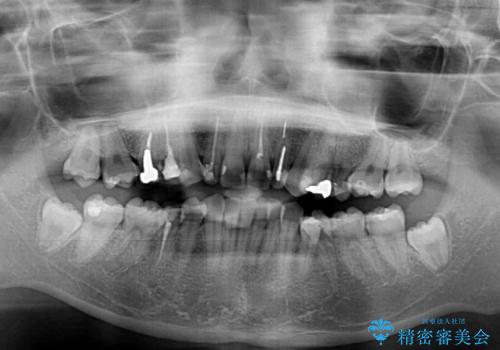

- 下顎の歯列から飛び出した小臼歯を気にして来院された患者様です。

歯列以外に、上顎左右側切歯が矮小歯であり、上顎4前歯は失活していたため、矯正治療で歯列を整えるとともに上顎前歯の幅を調整し、矯正治療後にオールセラミッククラウンにて審美歯科治療を行うこととしました。

矯正治療は、小臼歯1本分を歯列に納めないいけない状態であったため、表側のワイヤー装置にて行うこととしました。